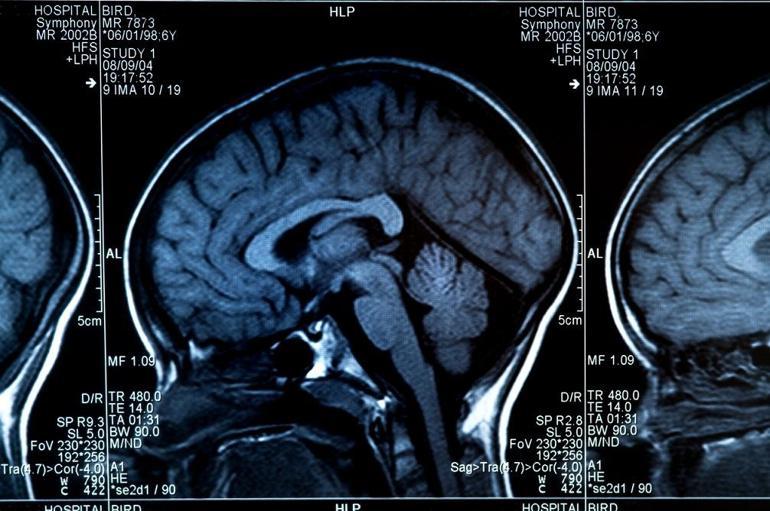

Demans, günlük yaşamı etkileyecek kadar şiddetli hafıza, dil, sorunları çözme ve diğer düşünme becerilerinin kaybını ifade eden genel bir terim. Zamanla sinir hücrelerini tahrip eden ve beyne zarar veren bir dizi hastalığın neden olabileceği bir sendrom.

Genellikle bilişsel işlevlerde, yani düşünceyi işleme yeteneğinde biyolojik yaşlanmanın olağan sonuçlarından beklenenin ötesinde bir bozulmaya yol açıyor. Bilinç etkilenmese de bilişsel işlevlerdeki bozulmaya genellikle ruh hali, duygusal kontrol, davranış veya motivasyon değişiklikleri eşlik ediyor ve bazen de öncesinde görülüyor.